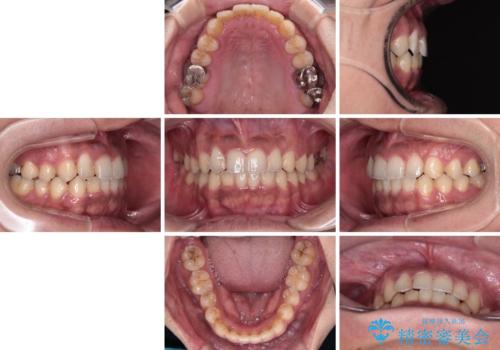

デコボコを治したい インビザラインによる矯正治療

- 前歯のデコボコを気にして来院された患者様です。

前歯が90度近く捻れていたため、しっかりと治すことを考えるとワイヤー矯正の方がおすすめではありましたが、本人の希望によりインビザラインを用いて矯正治療を行うこととしました。

途中2年強の来院がなく、改善されていたデコボコが元に戻ったり、装着時間が不足しており前歯のデコボコは十分に改善することはできませんでしたが、5年間の有効期限内で可能な限り歯列を整えることができました。